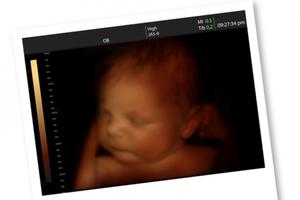

Based on the memoir by Planned Parenthood clinic director-turned-pro-life activist Abby Johnson, Unplanned opens on the crucial Saturday in September 2009 when, per Johnson’s conversion story, Abby (Ashley Bratcher, War Room) is asked to assist with an ultrasound-guided abortion and witnesses the image of a 13-week-old unborn child squirming in an apparent effort to avoid the vacuum cannula that proceeds to dismember its body piece by piece.

Caveat Spectator: Disturbing ultrasound images of an unborn child being dismembered; much medical gore and brief images of fetal parts; some cursing; a couple of sexual references. Mature viewing.